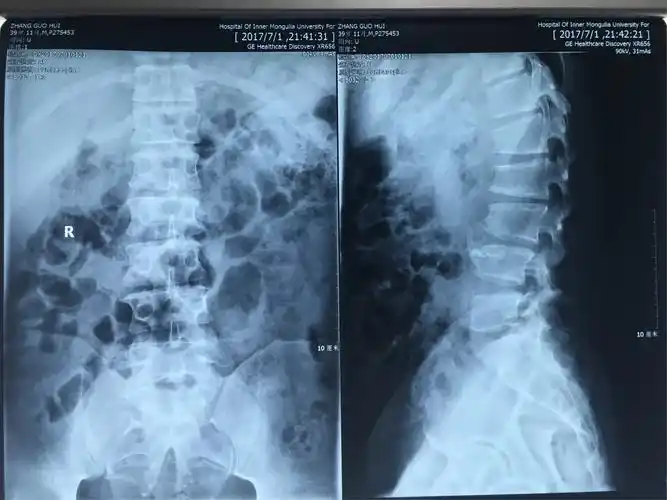

张xxx 男 39岁.腰二三椎间盘突出 严重挤压马尾神经病例